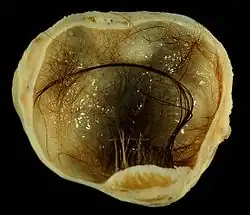

.jpg)

Immature, or solid, teratomas are the most common type of ovarian germ cell tumor, making up 40–50% of cases. Teratomas are characterized by the presence of disorganized tissues arising from all three embryonic germ layers: ectoderm, mesoderm, and endoderm; immature teratomas also have undifferentiated stem cells that make them more malignant than mature teratomas (dermoid cysts). The different tissues are visible on gross pathology and often include bone, cartilage, hair, mucus, or sebum, but these tissues are not visible from the outside, which appears to be a solid mass with lobes and cysts. Histologically, they have large amounts of neuroectoderm organized into sheets and tubules along with glia; the amount of neural tissue determines the histologic grade. Immature teratomas usually only affect one ovary (10% co-occur with dermoid cysts) and usually metastasize throughout the peritoneum. They can also cause mature teratoma implants to grow throughout the abdomen in a disease called growing teratoma syndrome; these are usually benign but will continue to grow during chemotherapy, and often necessitate further surgery. Unlike mature teratomas, immature teratomas form many adhesions, making them less likely to cause ovarian torsion. There is no specific marker for immature teratomas, but carcinoembryonic antigen (CEA), CA-125, CA19-9, or AFP can sometimes indicate an immature teratoma.[32]

Stage I teratomas make up the majority (75%) of cases and have the best prognosis, with 98% of patients surviving five years; if a Stage I tumor is also grade 1, it can be treated with unilateral surgery only. Stage II though IV tumors make up the remaining quarter of cases and have a worse prognosis, with 73–88% of patients surviving five years.[32]

Mature teratoma (dermoid cyst)

Mature teratomas, or dermoid cysts, are rare tumors consisting of mostly benign tissue that develop after menopause. The tumors consist of disorganized tissue with nodules of malignant tissue, which can be of various types. The most common malignancy is squamous cell carcinoma, but adenocarcinoma, basal-cell carcinoma, carcinoid tumor, neuroectodermal tumor, malignant melanoma, sarcoma, sebaceous tumor, and struma ovarii can also be part of the dermoid cyst. They are treated with surgery and adjuvant platinum chemotherapy or radiation.[32]